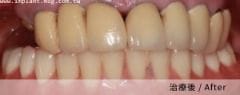

實際案例分享

案例三

另外,牙肉萎縮嚴重的病人也適合接受 All-on-4 / 6 全口重建,其使用的假牙可模擬牙肉部分,以完美的牙、肉比例加以擴充,安裝後美觀加分,效用超越傳統活動式假牙。

5. 模仿天然骨頭隆起的形狀,重現自然的唇形,擬真人工牙齦,減少齒間黑三角更美觀。